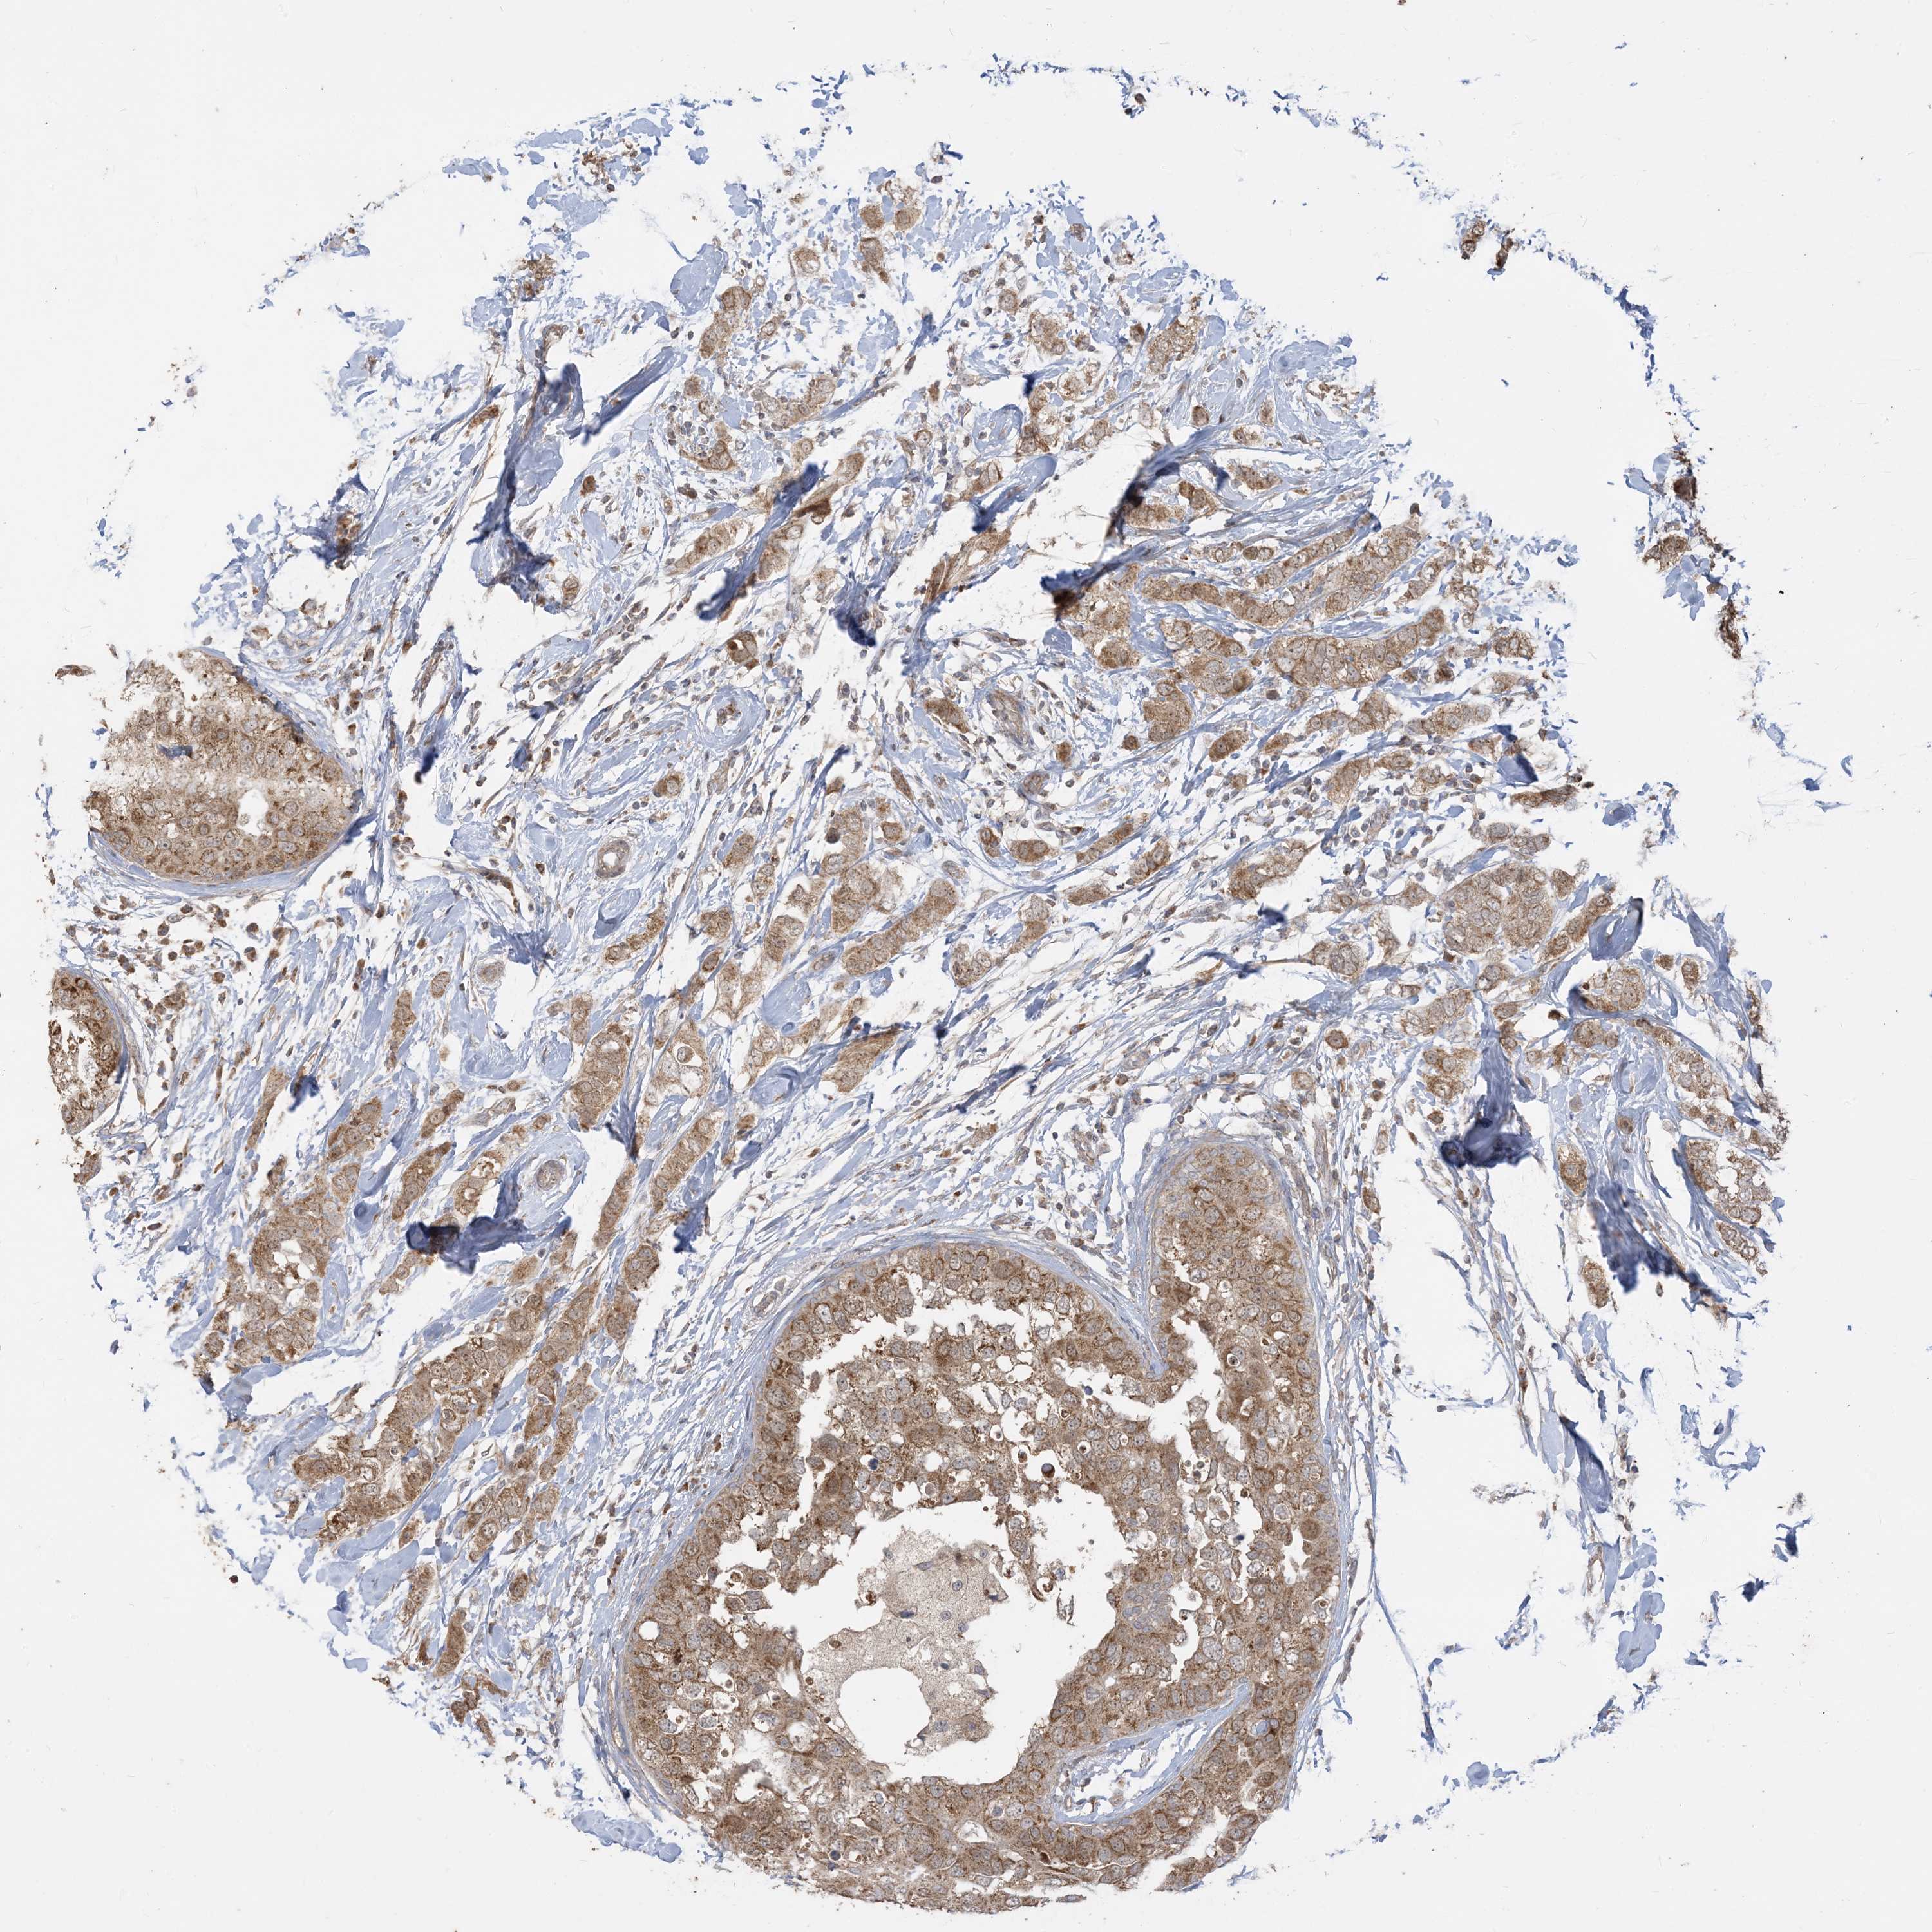

CANCER BREAST CANCER Show tissue menu

BRCA TCGA BRCA VALIDATION PROTEIN EXPRESSION